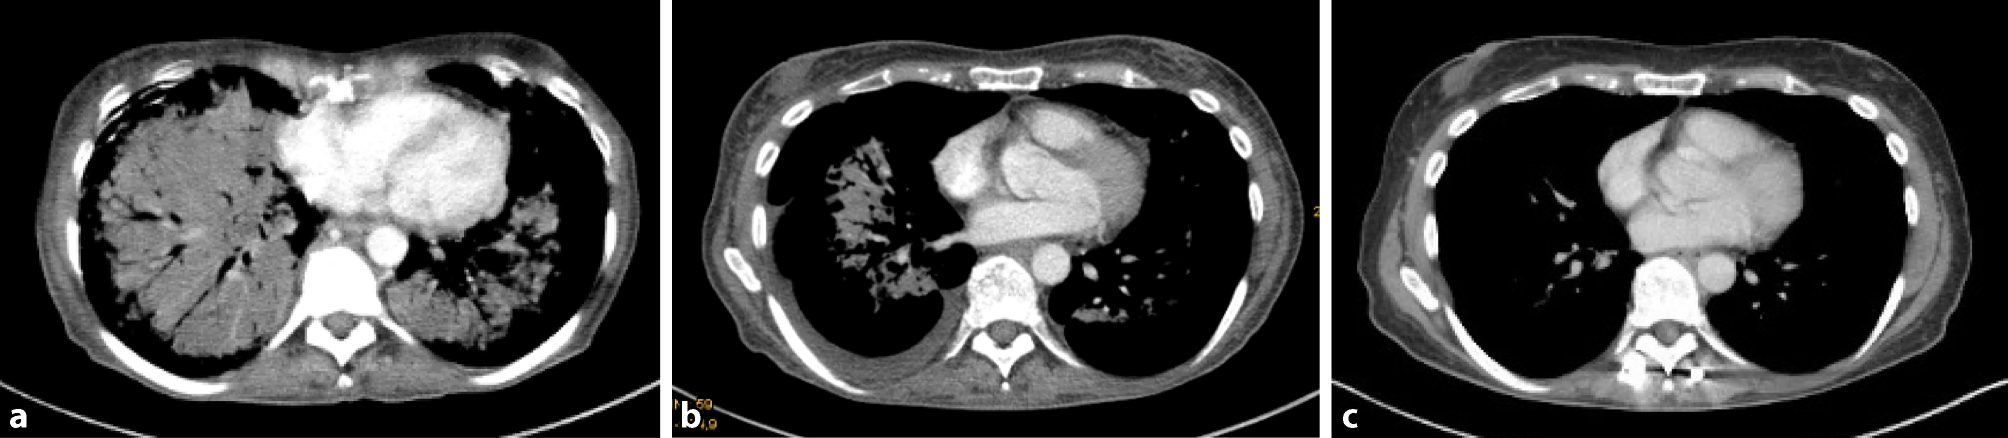

A 55-year-old woman first presented to a different department in August 2017 due to persistent cough with sputum, loss of weight and night sweat since one month. Medical history comprised bronchial asthma and positive smoking status with 15 pack–years. Arterial oxygen saturation was lowered and chest X‑ray revealed micronodular pulmonary lesions atypical for an infection. In the computer tomography (CT) scan of thorax and abdomen multiple, partly confluating lesions in the lungs (Fig. 1a), liver and pancreas were detected, as well as suspicious peritoneal and osseous metastases.

Fig. 1

Course of disease remission delineated by computed tomography of thorax: a at initial diagnosis, disseminated pulmonary metastases; b after one cycle of chemotherapy, partial remission; c one year after high-dose chemotherapy with autologous stem cell transplant, complete remission

Considering the young patient age, good pre-existing general condition and disseminated illness, we decided for subsequent polychemotherapy and stem cell transplantation. In September 2017, the patient received a preliminary phase with vinblastine (3 mg/m2 on day 1) and dexamethasone (40 mg on days 1–3), followed by primary chemotherapy with six cycles of cyclophosphamide (750 mg/m2 on day 1), doxorubicin (50 mg/m2 on day 1), vincristine (1.4 mg/m2 on day 1), and prednisolone (40 mg/m2 on days 1–5) (CHOP). The first cycle already led to a good partial remission (Fig. 1b and 2b); oxygen demand was reduced to two liters per minute. After reaching complete remission and successful stem cell apheresis, high-dosage therapy with carmustine (300 mg/m2 on day 1), cytarabine (400 mg/m2 on days 2–5), etoposide (200 mg/m2 on days 1–5), and melphalane (120 mg/m2 on day 6) with subsequent autologous stem cell transplantation was administered in May 2018. At the present time, one year later, the patient is in excellent general condition without oxygen demand and complete remission is still persisting (Fig. 1c and 2c).